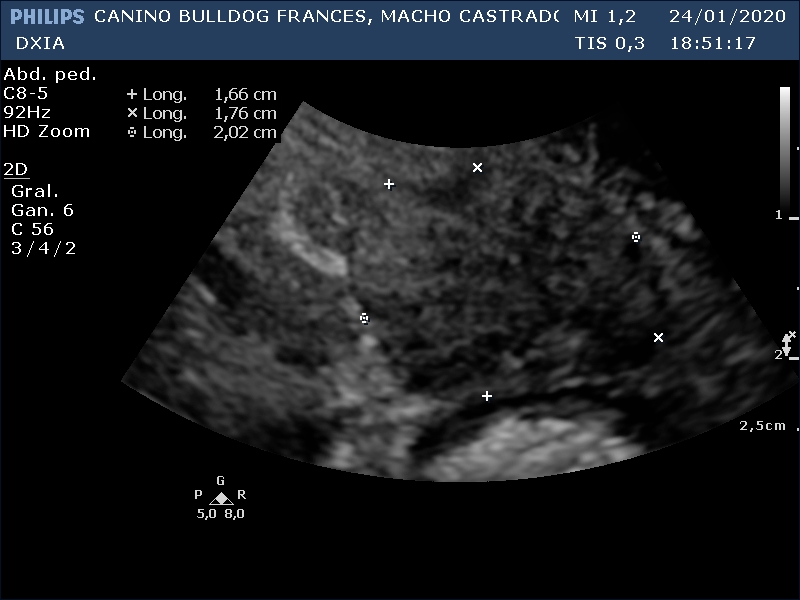

RONY

Del informe ecográfico de Rony se destaca la existencia de varias alteraciones:

Neoformación en la que se observa estructura en capas en su zona dorsal. Se realiza PAF ecoguiada.